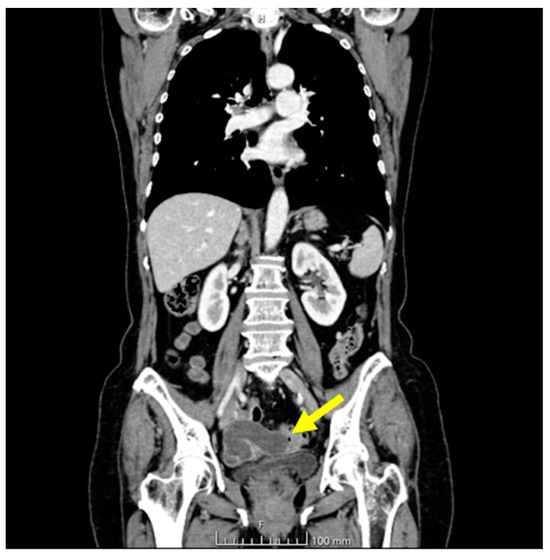

3.6.1. Case 1

3.6.2. Case 2